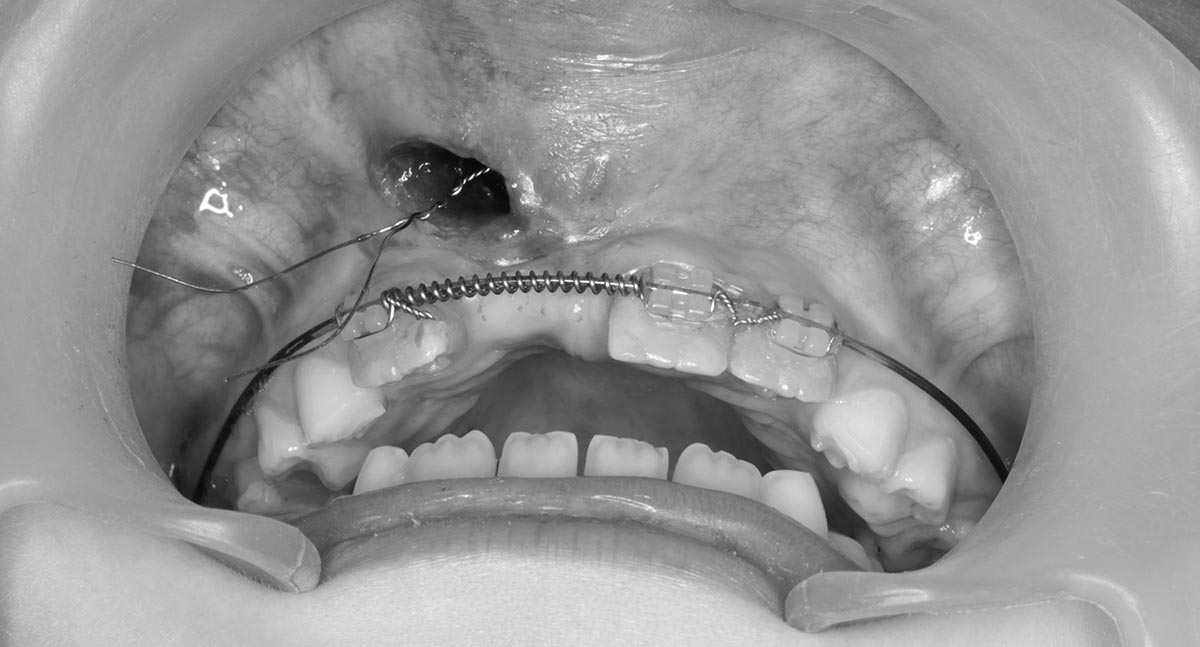

Лоскутная пластика десен является процедурой для восстановления или увеличения объема мягких тканей десен, проводимой путем переноса ткани из другого участка полости рта или с использованием донорских или синтетических материалов. Процедура помогает восстановить эстетику улыбки, улучшить защиту зубов и способствует здоровью десен. Она предусматривает тщательную подготовку, точную переноску ткани и послеоперационный уход для обеспечения успешной приживки и достижения желаемых результатов.

После коррекции десен врач закрепляет ткани швами, что стабилизирует их в новом положении и поддерживает правильную форму. Это обеспечивает оптимальное приживание трансплантированных тканей и снижает риск осложнений.